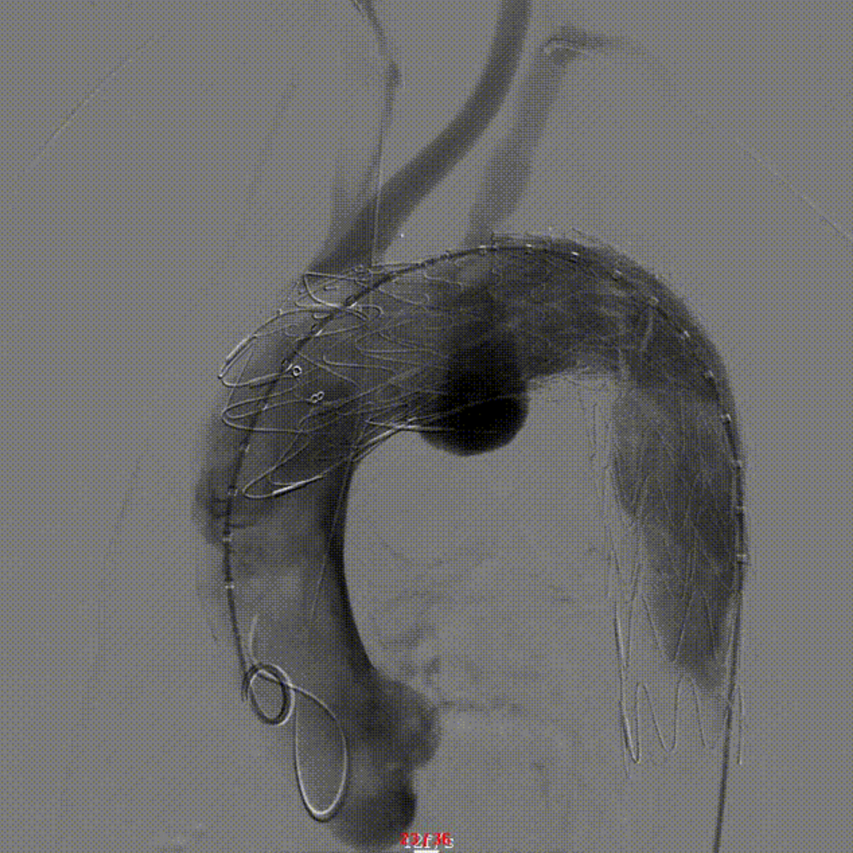

【病例2】主动脉B型夹层,

2016年外院TEVAR术后II型内漏

术后8年随访发现假腔明显扩大,最大直径达96mm,伴胸背疼痛,有手术干预指征。

再干预方案:弹簧圈栓塞分支血管(LSA栓塞),覆膜支架+封堵器+弹簧圈覆盖左肾动脉破口。

修复结果:进入假腔血流明显减少,胸背疼痛症状明显缓解。

二次手术前CTA

LSA弹簧圈栓塞

造影内漏消失